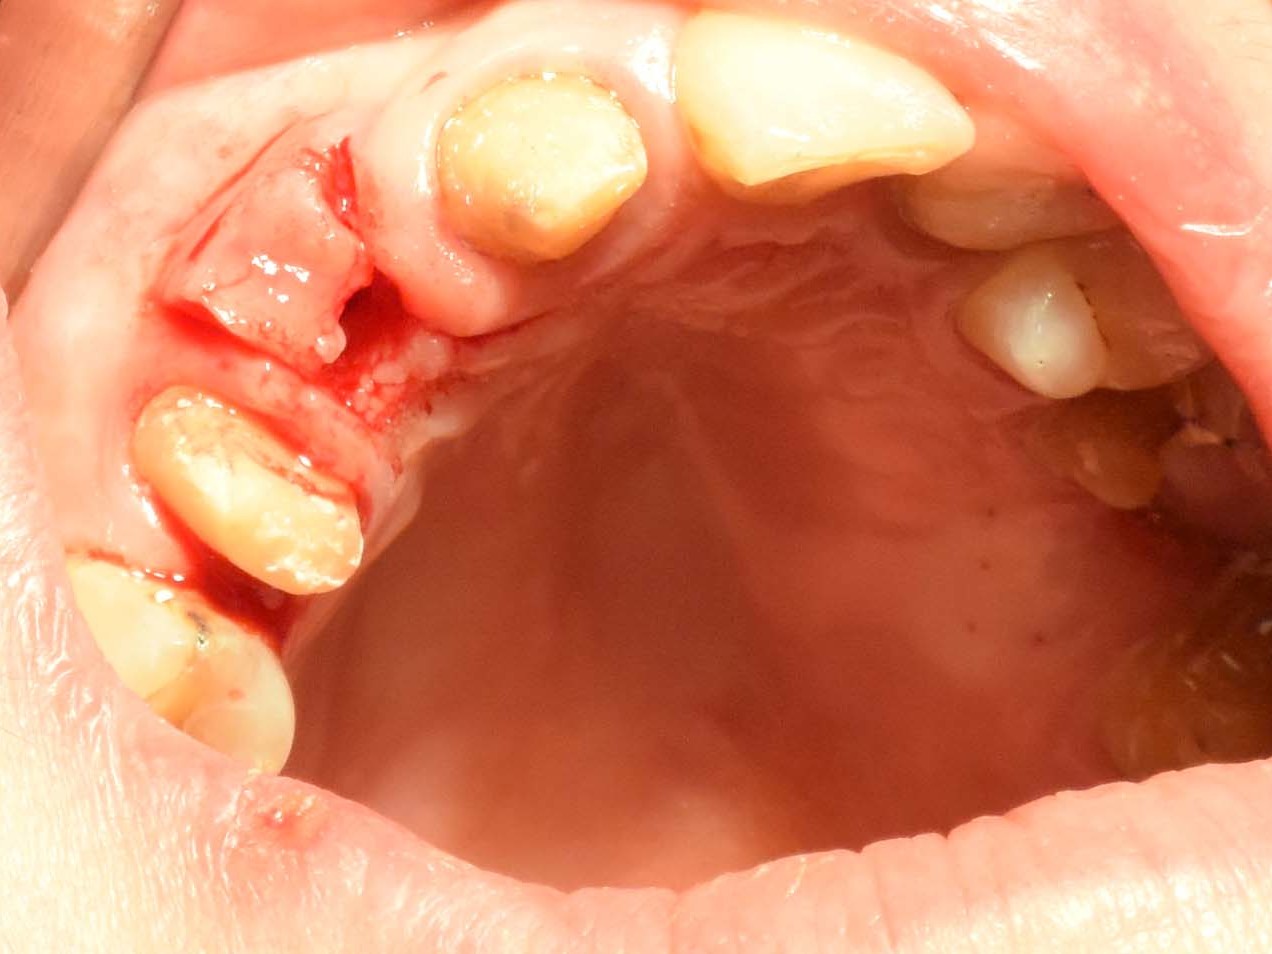

Unter oraler Antibiose mittels Clindamycin 600mg 2 x/Tag erfolgte zunächst die typische minimalinvasive Präparation des Mukoperiostlappens unter Erhalt der Papillen zu den Nachbarzähnen in Regio 12 (Abb. 6), nachdem die Brücke von Zahn 11 nach 14 entfernt wurde (Abb. 7). Wegen Nichtanlage von 13 steht der Zahn 14 in dessen Region. Seinerzeit wurde der Zahn 14 zur Aufnahme einer entsprechenden Eckzahnkrone umgestaltet. Die Implantatbettpräparation (Abb. 8 und 9) für das Straumann PURE Ceramic Implantat (Ø 3,3 mm, Länge 12mm) erfolgte gemäß dem Straumann Guided Surgery Protokoll. Die abschließende Implantatinsertion wurde dem Protokoll für die Straumann PURE Ceramic Implantatlinie gemäß durchgeführt (Abb. 10 und 11). In der Implantatsetzungsregion des zweiten Quadranten wurde zunächst die Inlay-Brücke von Zahn 25 nach 27 entfernt. Seitens des zahntechnischen Labors wurde das Zahninlay von Zahn 27 von der Brücke getrennt und wieder inkorporiert. Nach der Extraktion des tief zerstörten Zahnes 25 erfolgte die typische Mukoperiostlappenpräparation. Nach Darstellung des Insertionssitus kam die massive vestibuläre Knochendefizitsituation in Regio 26 zur Darstellung (Abb. 12). Zunächst wurde die Präparation der Implantatstollen in Regio 25 und 26 gemäß dem Straumann Guided Surgery-Protokoll durchgeführt. In Regio 25 wurde ein Straumann Bone Level Roxolid Implantat (Ø 4,1 mm, Länge 12mm) als Sofortimplantation eingesetzt (Abb. 13 und 14). In Regio 26 wurde ein Knochenring CHB¹⁶ zur Augmentation des vestibulären Knochendefizits entsprechend des ossären Knochenabhanges angeschrägt und in der Höhe eingekürzt (Abb. 15). Die Anpassung des homologen Ringes erfolgt unter Fixierung mit der bonering fix-Zange und Anwendung einer 10-mm-Diamanttrennscheibe (Abb. 16).

Abb 6 Zustand nach Typischer Lappenpräparation

Abb. 6: Zustand nach Typischer Lappenpräparation